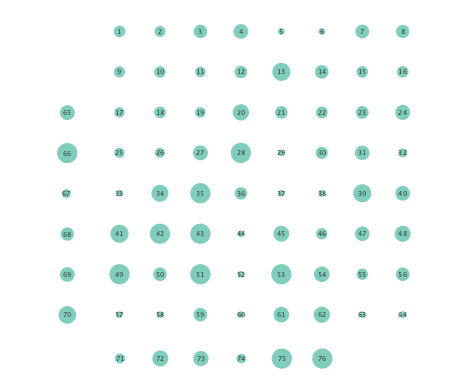

Moreover, the performance of K-SVARM with data-driven kernel selection was also tested. Figure 7 illustrates the per node degree as well as the closeness centrality of networks inferred from preictal and ictal phases. Consistent with Figures 3 and 6, Figure 7 again reveals universal decrease in node degrees as well as closeness centrality at seizure onset.

Network density refers to the number of actual edges divided by the number of potential edges, while the global clustering coefficient is the fraction of connected triplets that form triangles, adjusted by a factor of three to compensate for double counting. On the other hand, network diameter is the length of the longest geodesic, excluding infinity. Table I shows that networks inferred via the K-SVARM exhibit lower network cohesion after seizure onset, as captured by network density, global clustering coefficient, and average number of neighbors, while the network diameter increases.

These changes provide empirical evidence that the brain network becomes less connected, and diffusion of information is inhibited after the onset of an epileptic seizure. Also interestingly, it turns out that the number of self-loops significantly decrease during the ictal phase for networks inferred using the K-SVARM. Note that in this experiment, only connections to the previous time interval are considered (), while is constrained to have no self-loops. As a consequence, existence of a self loop reveals a strong temporal dependence between measurements at the same node. In fact, a drop in the number of self loops implies a lower temporal dependence between successive ECoG samples, a phenomenon that was not captured by the linear SVARM.